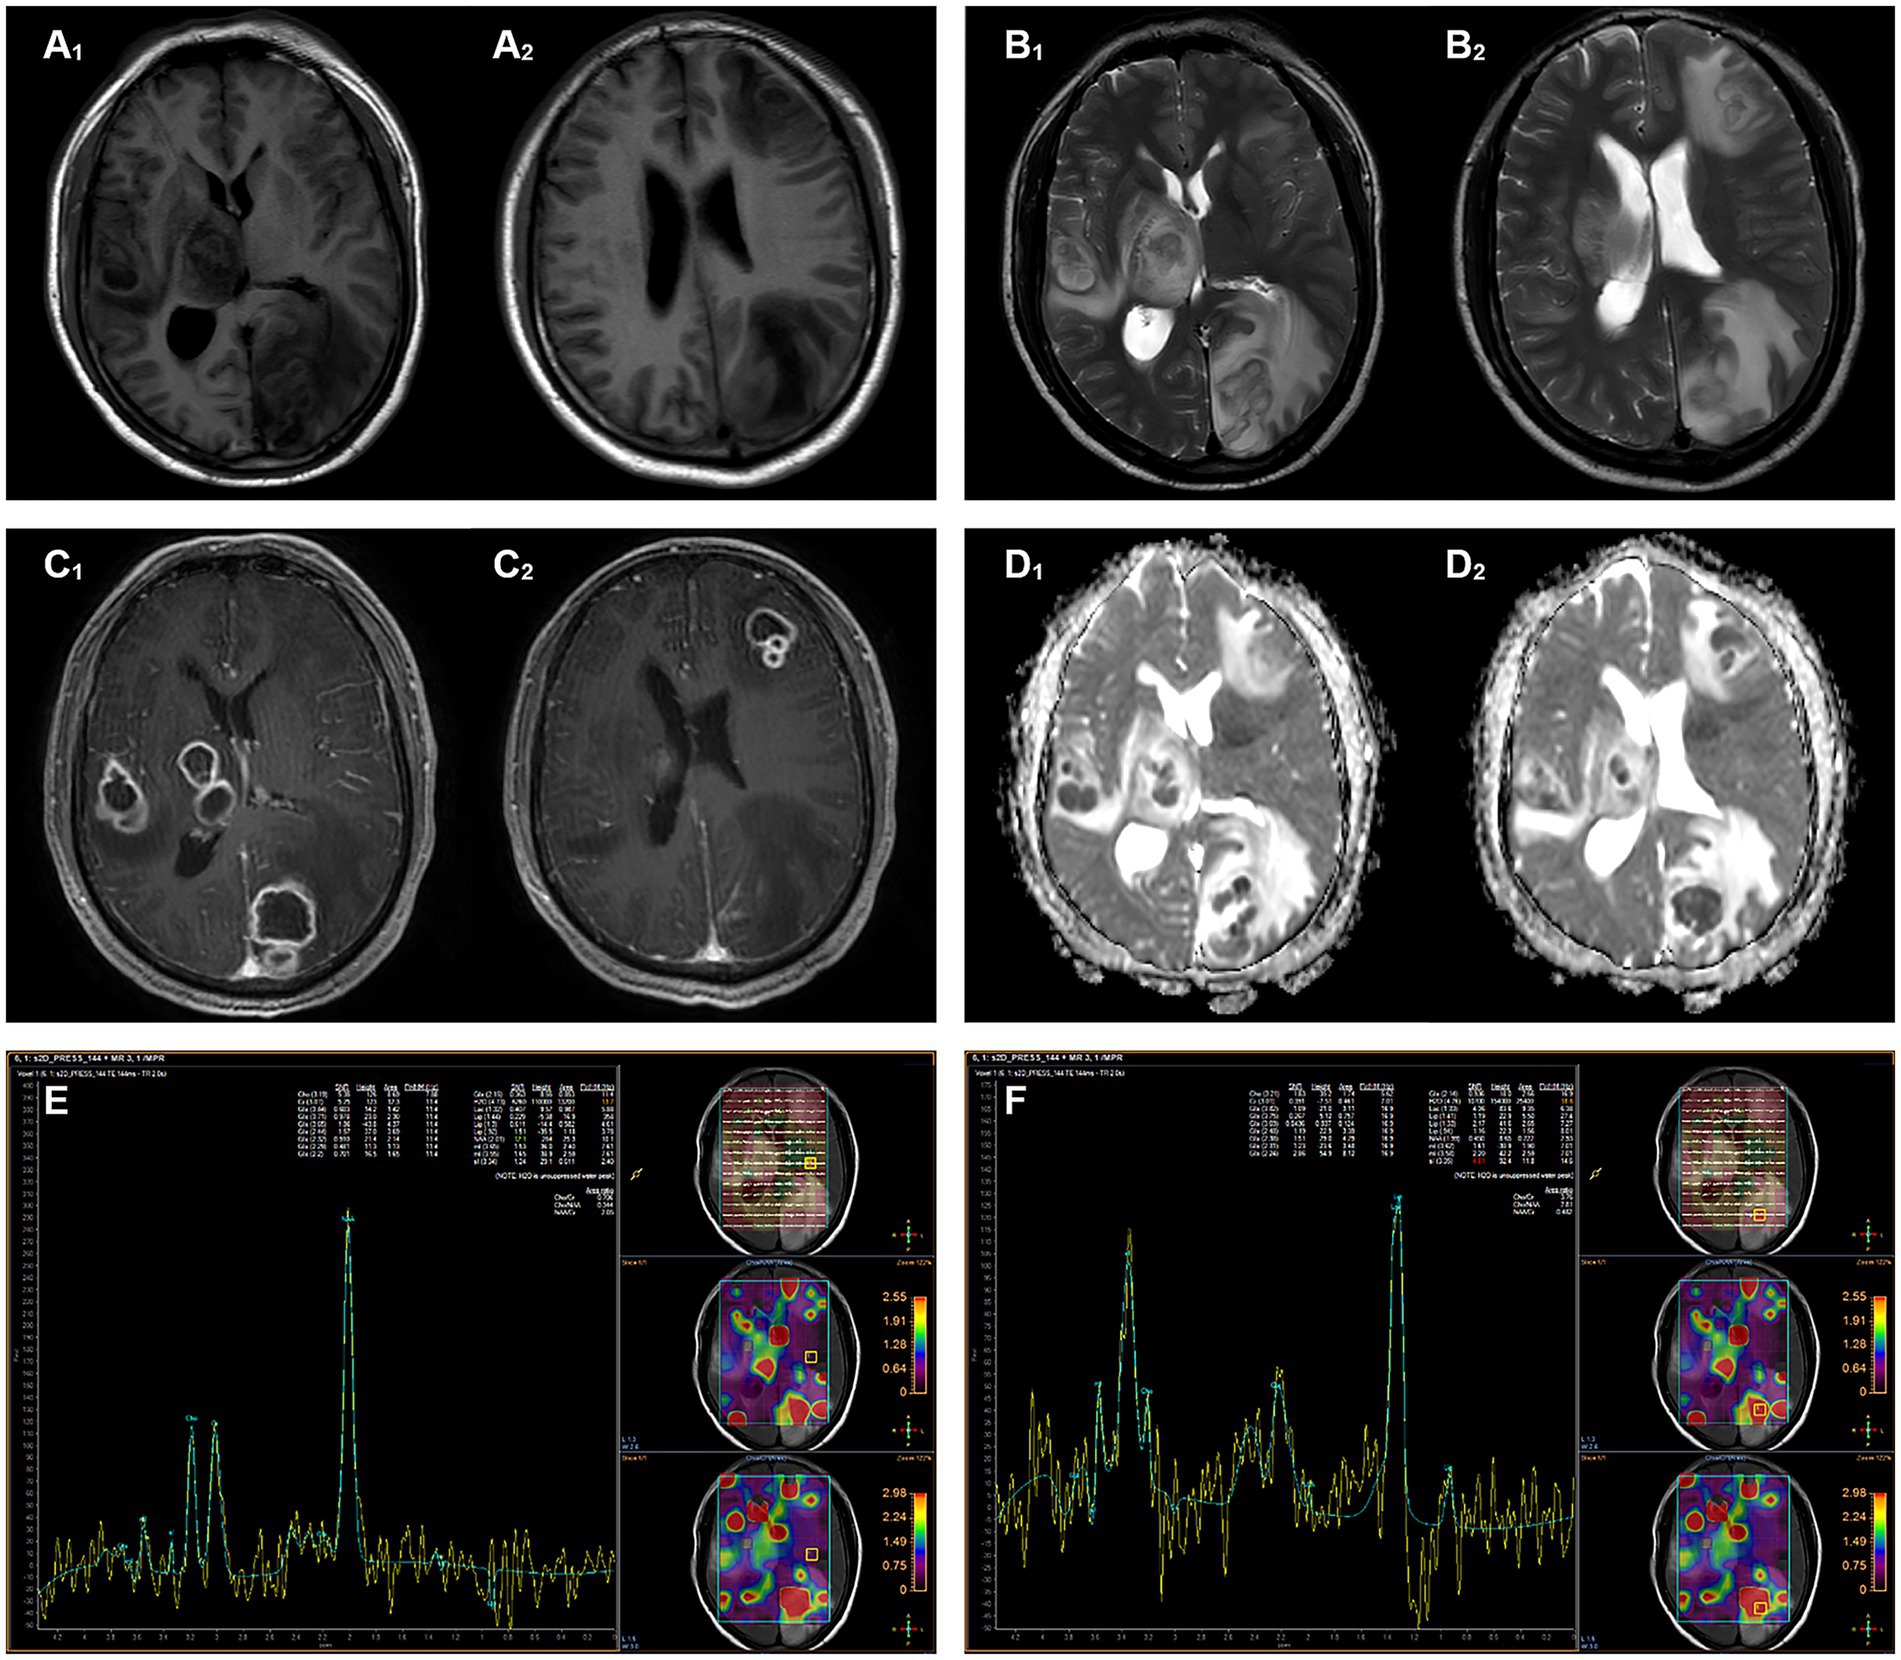

After 3 days of aerobic culture of the abscess secretions, white villous colonies were observed on blood agar, Gram staining showed branching filamentous bacteria, and modified acid-fast staining was weakly positive (Figure 2). N. asiatica was further identified by matrix-assisted laser desorption ionization-time-of-flight mass spectrometry (MALDI-TOF MS). The anti-infective treatment regimen was adjusted to include compound trimethoprim/sulfamethoxazole (TMP-SMX) and acyclovir.

Figure 2

(A) A pale yellow pus was aspirated during the operation, (B) White bacterial colonies grown on a blood agar plate, (C) Gram-positive branching filaments observed in a cultured colony, (D) Weakly positive modified acid-fast staining of a cultured colony.